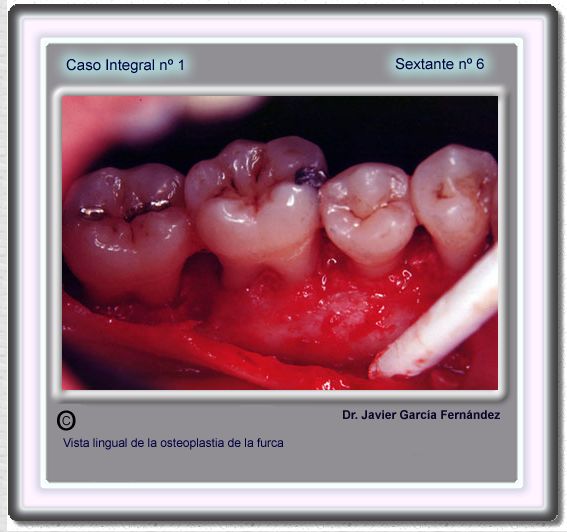

image 107